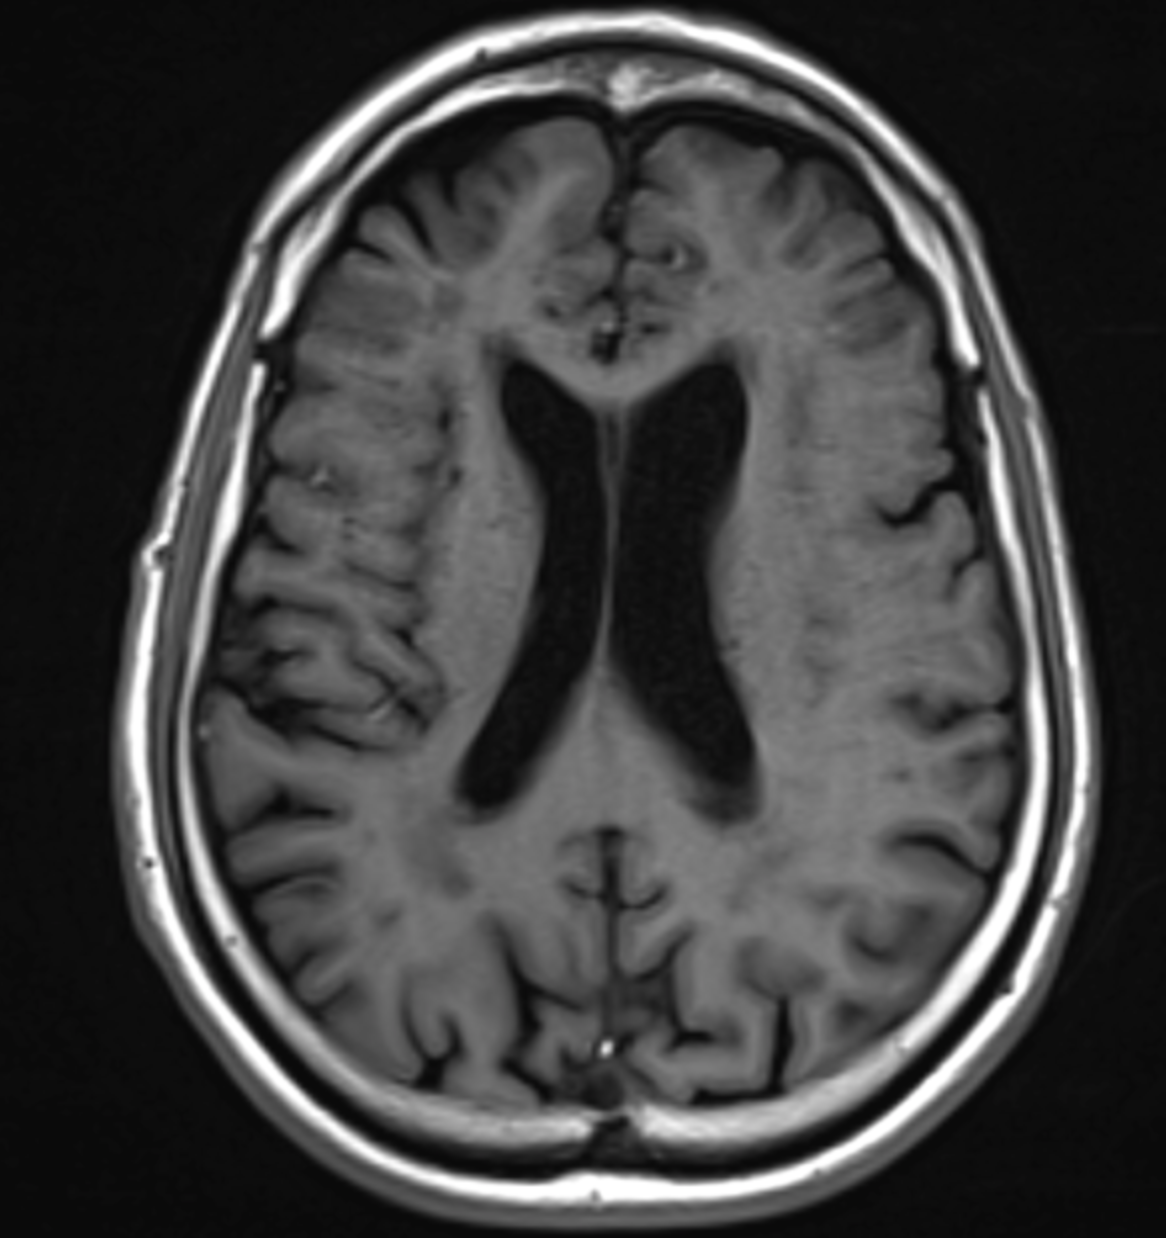

Quelle est la séquence de cet IRM ?

T1 Gado